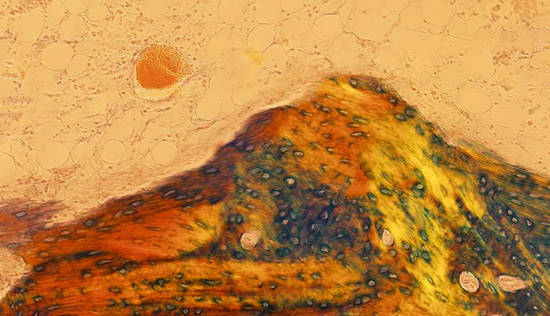

毫无疑问,第一大看点,当属书中收录的85幅显微摄影作品。单看五个章节的标题,就足以想象作品之意境。

作者试图通过给生物学和医学带来巨大革命的显微镜,去探寻生命的“无穷之境”。本书看似一本艺术画册,但其展示的“风景”却来自人体的组织和细胞,来自一位经常与“生和死”打交道的病理医生的独特视角。它可引发人们对宏观“大宇宙”和人体“小宇宙”的哲学思考,感叹和领悟中华文化中有关“天人合一、道法自然”的深刻内涵。

《狐仙》

牙齿磨片局部的镜像,X100,偏振光,2014